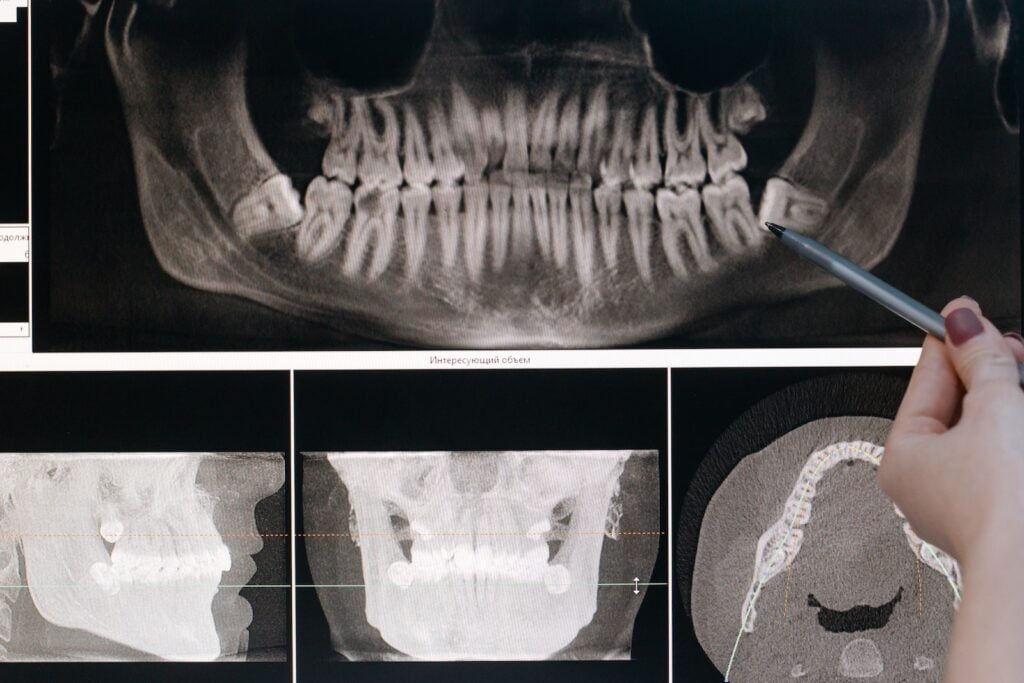

Consulta y Planificación

Antes de someterse a un procedimiento de implante de mentón, es crucial programar una consulta con un plástico calificado. cirujano. Durante esta consulta, el cirujano evaluará su estructura facial, analizará sus objetivos y expectativas y determinará el tamaño y la forma de implante más adecuados para usted. Este enfoque personalizado asegura que el resultado final complementará sus características faciales únicas.